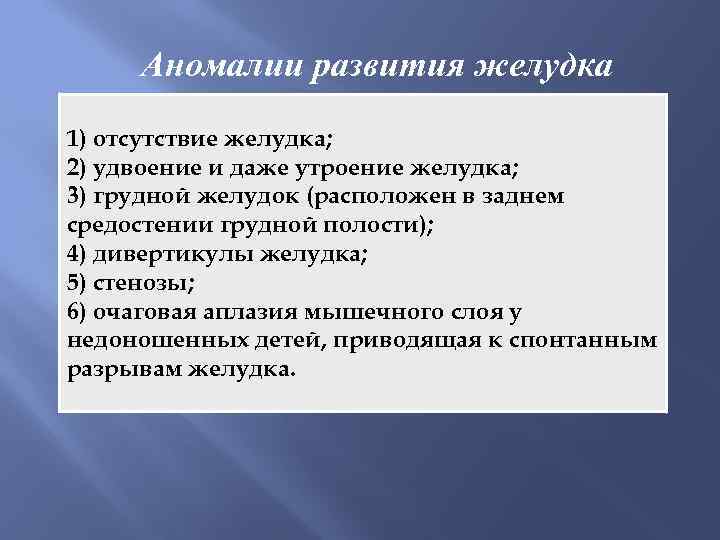

Аномалии развития желудка 1) отсутствие желудка; 2) удвоение и даже утроение желудка; 3) грудной желудок (расположен в заднем средостении грудной полости); 4) дивертикулы желудка; 5) стенозы; 6) очаговая аплазия мышечного слоя у недоношенных детей, приводящая к спонтанным разрывам желудка.

Аномалии развития желудка 1) отсутствие желудка; 2) удвоение и даже утроение желудка; 3) грудной желудок (расположен в заднем средостении грудной полости); 4) дивертикулы желудка; 5) стенозы; 6) очаговая аплазия мышечного слоя у недоношенных детей, приводящая к спонтанным разрывам желудка.